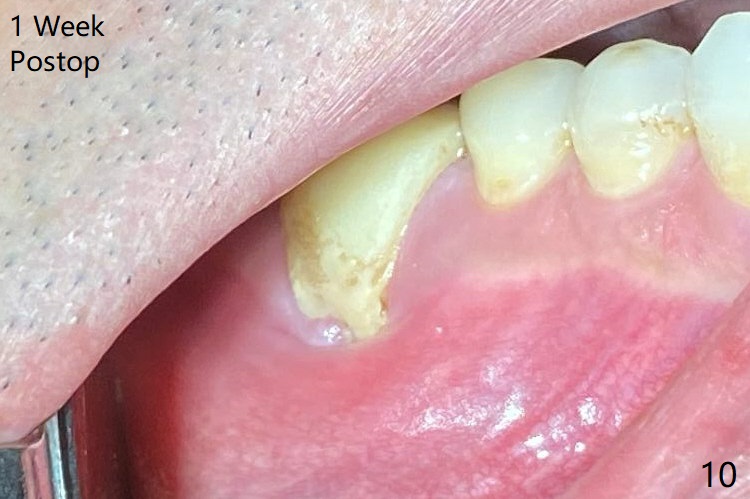

When the tooth #30 is extracted, the gingiva buccal to the septum (S in Fig.1,2 (P: papilla between the mesial and distal roots)) collapses. The latter is fixed with placement of a 4.5x11.5 mm implant (with guide), a 5.2x4(5) mm cemented abutment (Fig.3) and mixture of cortical bone (125μm – 850μm) and cortical/cancellous bone (.5-1 mm) with PRF (sticky bone, B in Fig.4-6). After placement of 2 pieces of PRF membrane over the bone graft, a temporary crown is fabricated to cover the buccal defect (Fig.7 T). Approximately 7.5 mm of the buccal threads are covered by the thick layer of bone graft (Fig.8 B). It is amazing to expect that the bone graft will turn into the buccal plate. It would be better if a narrower implant (4 instead of 4.5 mm) were placed more lingually or there were < 4 mm implant thread exposure (Fig.9). The gingiva reacts to the provisional nicely 7 days postop (Fig.10). The provisional will be removed for modification in 1 month. The patient complains of bad smell from the provisional 2 weeks postop. The provisional is removed. The distal socket (Fig.11 D) is healing, whereas the buccal bone graft (Fig.12 B) seems not have been vascularized. Pedicled flaps (I) should be transferred to cover the buccal bone graft. The margin of the provisional is polished, becomes short, and covered by periodontal dressing, which dislodges 2 days later. One week later, granulation tissue is forming apically with use of oral antibiotic and water jet (Fig.13 *). The bad smell reduces. The superficial loose bone graft changes colar and becomes detached 1 month 10 days postop. The temporary crown with the shortened buccal shelf is reseated for self cleansing or reapplication of PRF if needed (Fig.14).